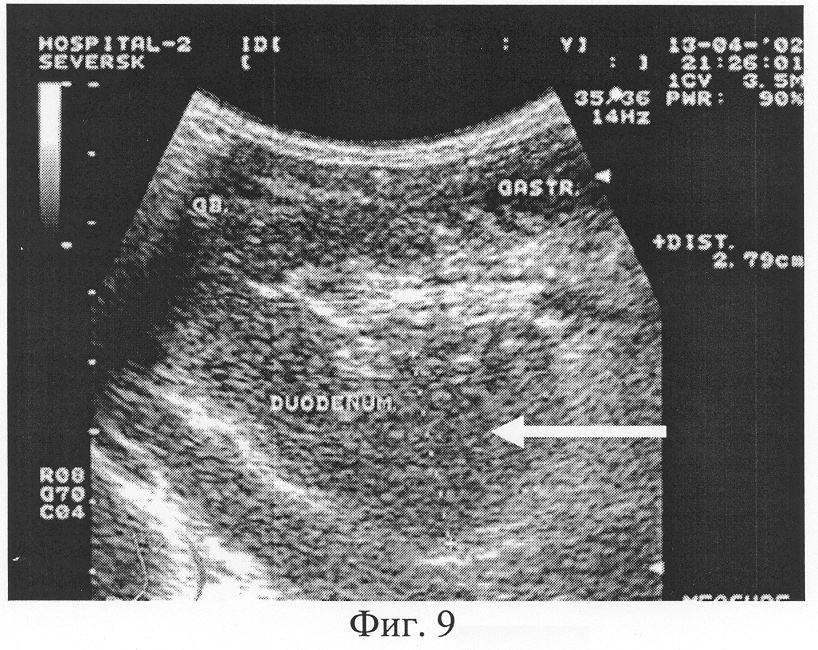

Следующий этап предлагаемого способа ультрасонографии двенадцатиперстной кишки – определение зоны распространения содержимого в двенадцатиперстной кишке натощак. Проводится ультразвуковое трансабдоминальное исследование ДПК на всем ее протяжении по общепринятой описанной методике [1-3] и в случае регистрации содержимого в нижней горизонтальной части двенадцатиперстной кишки натощак определяют нарушение ее моторно-эвакуаторной способности (стаз содержимого) (Фиг.9).

Фиг.9. Больная В., 30 лет. Ультразвуковая картина дуоденостаза при трансабдоминальной гастросонографии в виде визуализации верхней и нижней горизонтальной ветви кишки, увеличения просвета ДПК до 28 мм, сглаженности складчатости слизистой, анэхогенного содержимого и снижения перистальтической активности кишки.